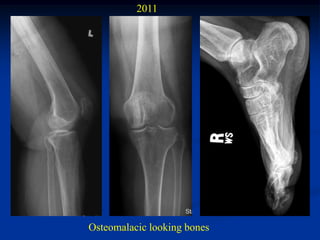

2011

Osteomalacic looking bones